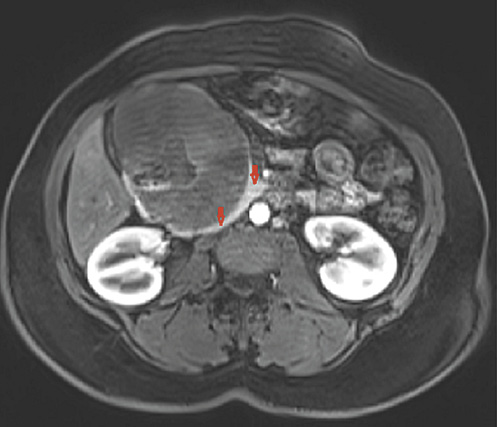

An abdominal computed tomography scan and magnetic resonance imaging showed a mixed solid and cystic lesion in the head of the pancreas approximately 12 × 10 cm in diameter. This mass was well delimited by a capsule that presented enhancement on the arterial phase. The tumor was in direct proximity to the duodenum and contained an air cavity within it that was filled by oral contrast, which was compatible with a fistulous tract (Fig. 2, 3). There was no dilation of the bile or pancreatic ducts on the magnetic resonance cholangiopancreatography.

Fig. 3 Abdominal magnetic resonance image showing a mixed solid and cystic well-defined lesion in the head of the pancreas. This mass was well delimited by an enhancing thick fibrous capsule (arrows).